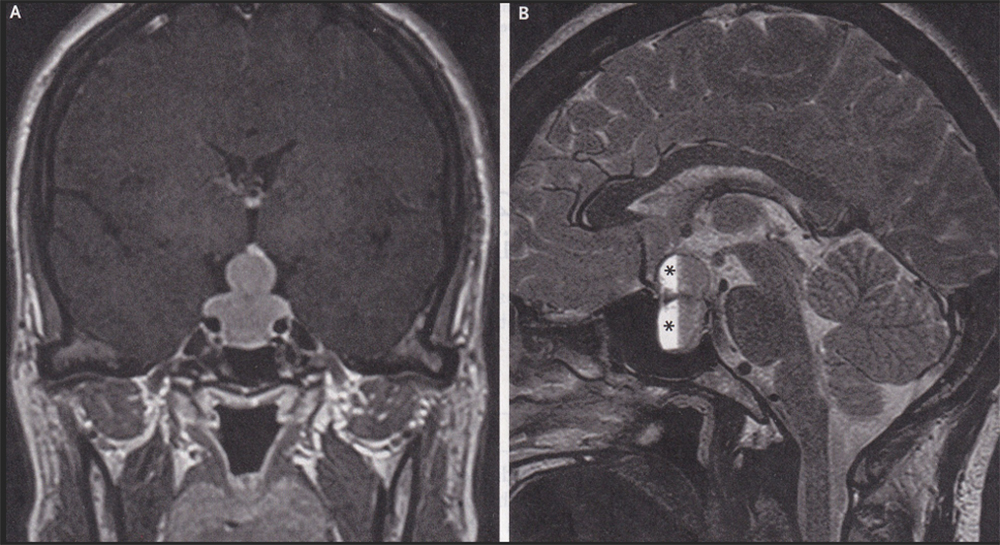

This case is from Wenzhou People’s Hospital in Wenzhou, China. A previously healthy 47-year-old woman presented to the neurology clinic with a one-month history of worsening headaches associated with blurry vision, galactorrhea (milk secretion from the breast in a non-pregnant woman), and irregular menstrual cycles. Physical examination was notable for reduced visual acuity of 20/50 in both eyes, with normal visual fields and eye movements. An MRI scan of the head showed an enlarged pituitary gland (gland at the base of the brain that controls many endocrine systems) protruding from the sella tursica. The sella tursica, Latin for Turkish saddle, is a saddle-shaped depression in the sphenoid bone, which comprises both part of the base of the brain and roof of the sinuses and is found in both humans and apes. Normally, the pituitary sits in the bottom of the sella tursica and is connected to the brain via an upward stalk. In this scan, the enlarged pituitary extends upward into the suprasellar cistern and is compressing the optic chiasm (where the optic nerves cross each other with the pituitary stalk in the center). This is known as the “snowman sign” (see Panel A, center).

In Panel B, at asterisks, intrapituitary hemorrhage is noted. The snowman sign occurs when a slow-growing tumor that originates in the sella tursica gets indented by the roof of the sella in its upward growth. Often, although not in this case, a pituitary tumor like this will press on the optic nerves causing bitemporal hemianopsia. That is the loss of the outer side of the visual field in both eyes. It is the outer side of the visual fields because the optic nerves have already crossed each other, so signals from the outer visual fields are now on the inner side of each nerve, with the pituitary tumor in the middle. In fact, in the absence of trauma, bitemporal hemianopsia is pathognomonic (nothing else causes it) for a pituitary tumor.